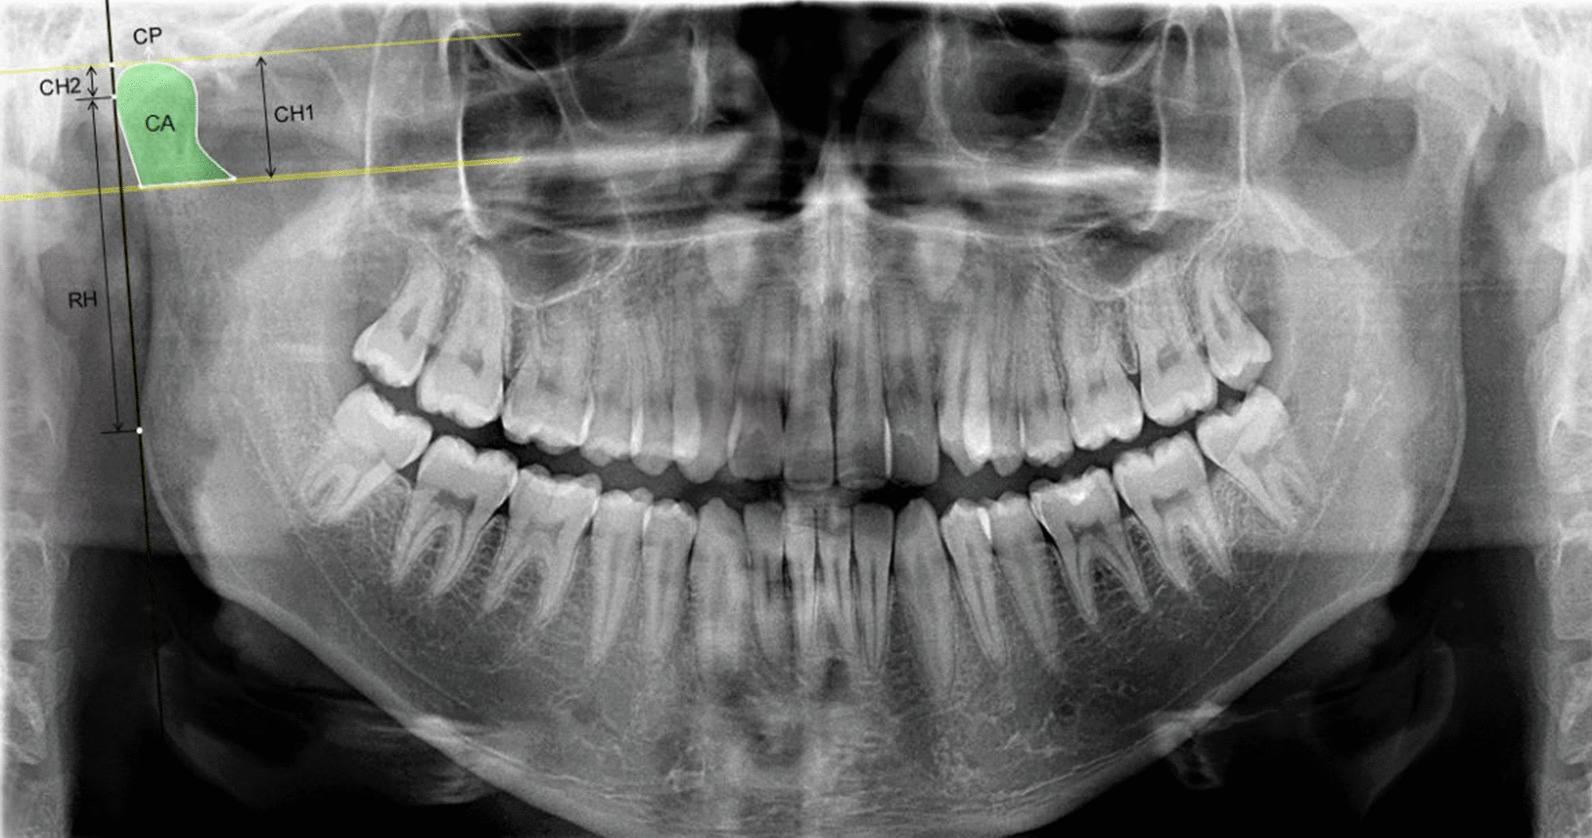

Fig. 2.

Dental panoramic radiograph showing the selection of the condylar area (CA), the condylar perimeter (CP), the condylar height 1 (CH1), the condylar height 2 (CH2), the ramal height (RH) and the total height (CRH = CH2 + RH)